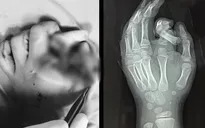

VTV.vn - Bệnh viện Đa khoa Xuyên Á Tây Ninh vừa thực hiện thành công ca phẫu thuật nối ngón tay đứt lìa cho nam bệnh nhân 51 tuổi bị tai nạn lao động.

Theo người nhà bệnh nhân T.V.C. (trú tại Gò Dầu, Tây Ninh), khoảng 19 giờ ngày 17/5, khi bệnh nhân đang cắt bánh tráng thì bất ngờ bị máy cắt vào ngón II, III tay trái. Tai nạn xảy ra đã làm đứt lìa ngón II, III trên bàn tay trái.

Ngay khi tiếp nhận bệnh nhân, các bác sĩ nhanh chóng cấp cứu, hội chẩn chuyên khoa đánh giá tình trạng tổn thương (may mắn là các phần chi đứt lìa được bảo quản tốt) và quyết định nối lại các ngón tay bị đứt bằng kỹ thuật vi phẫu nối mạch chi.

Bệnh nhân được chuyển lên phòng mổ. Ê-kíp phẫu thuật gồm đội Vi phẫu thuộc Khoa Chấn thương Chỉnh hình phối hợp cùng với các bác sĩ Khoa Phẫu thuật Gây mê Hồi sức đã tiến hành khâu nối mạch máu dưới sự hỗ trợ của kính hiển vi điện tử.

Sau hơn 4 tiếng tập trung tại phòng mổ, bằng kỹ thuật nối vi phẫu, các bác sĩ đã nối lại thành công mạch máu, thần kinh, gân cơ, xương các ngón tay cho bệnh nhân. Kết thúc phẫu thuật, kiểm tra ngón hồng hào, SpO2 của ngón II và III tay trái đạt yêu cầu từ 95 - 100%.